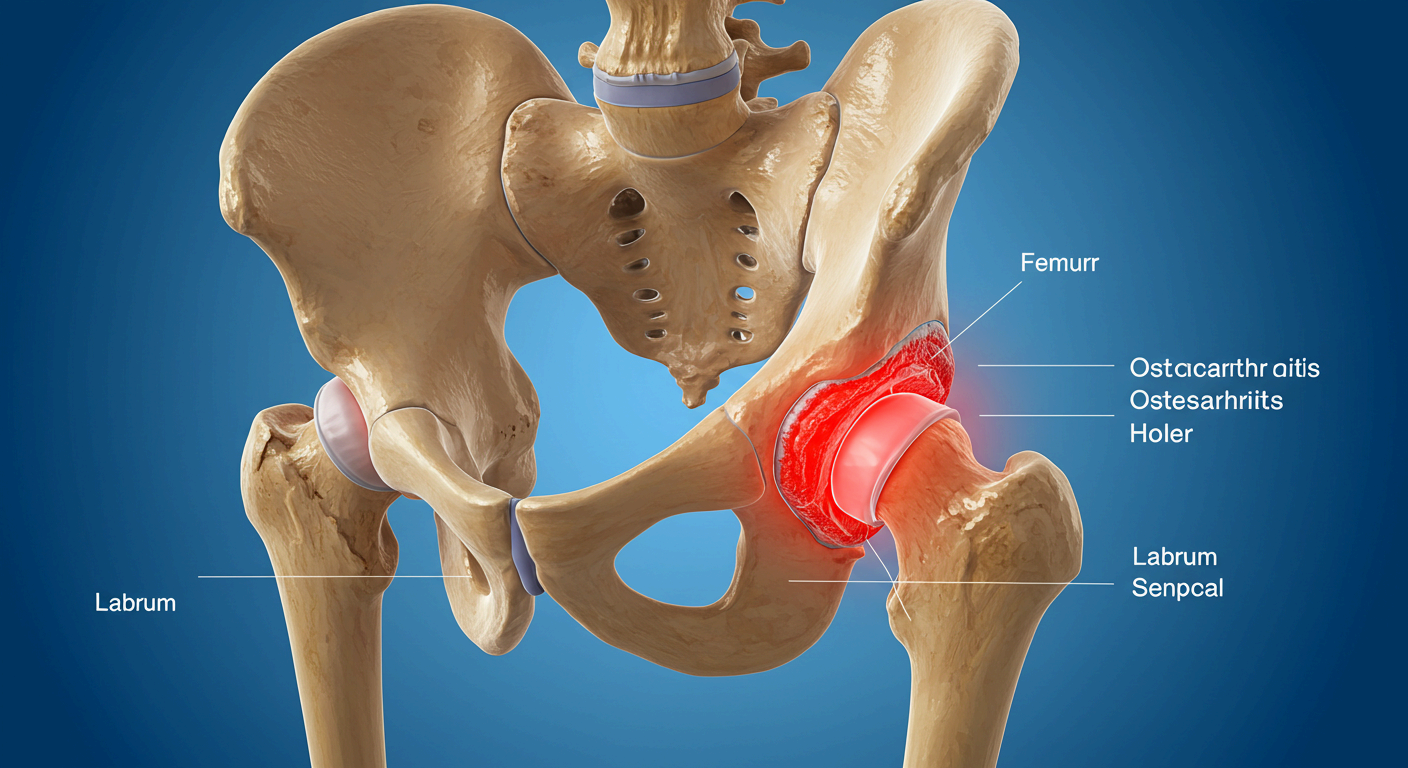

📌 퇴행성 고관절염

- 고관절 연골이 닳아 없어지며 뼈와 뼈가 직접 마찰됨

- 50대 이상에서 흔하며, 통증·운동 제한·관절 소리 등이 특징

📌 고관절 점액낭염

- 고관절 부근 점액낭에 염증이 생기며 눌렀을 때 통증이 심함

- 자주 눕는 자세나 운동 후 급성통증 발생 시 의심

📌 대퇴골두 무혈성 괴사

- 혈액 공급 부족으로 뼈 조직이 괴사되어 통증 유발

- 음주, 스테로이드 과다 사용 등도 원인이 될 수 있음